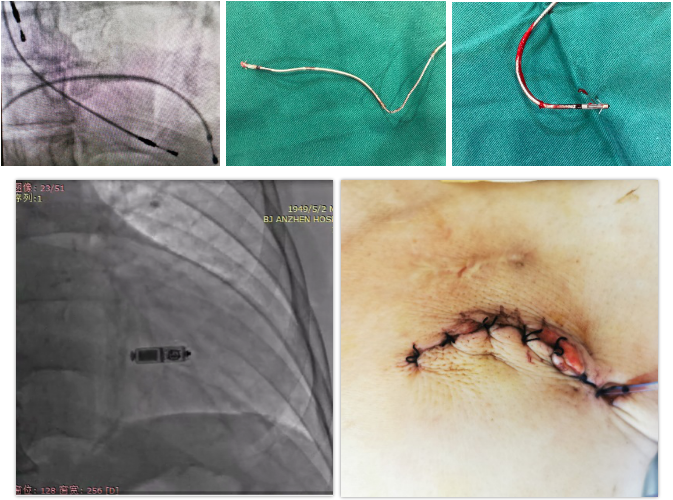

患者及家属签署知情同意书后行“一站式”临时起搏器植入术+起搏器囊袋清创术+起搏器取出术+起搏器电极拔除术+无导线起搏器植入术。手术过程中,手术科室、麻醉科、导管室、器械科、超声心动科和技术工程师建立了一个高效完备的多学科交叉体系,在心外科、体外循环的保驾护航下,有条不紊地实施手术。手术团队桥接置入临时起搏器电极,切开感染起搏器囊袋,电刀分离纤维包裹的电极,置入锁定钢丝,应用分离鞘管取出心房电极;但在拔除心室电极时却遇到了电极与锁骨下静脉严重黏连、反复尝试鞘管无法通过锁骨下静脉的困境,应用一般方法难以分离,且极易造成锁骨下静脉撕裂导致患者大出血危及生命,结合使用电刀进行囊袋分离极为困难的实际情况,团队及时换用激光鞘成功游离电极导线并成功拔出心室电极。应用万古霉素及过氧化氢溶液进行囊袋清创,同时植入Micra无导线起搏器,手术过程顺利。术后应用万古霉素(感染分泌物敏感性抗生素)治疗,复查床旁超声心动图未见异常,无并发症。

图3 “一站式”手术